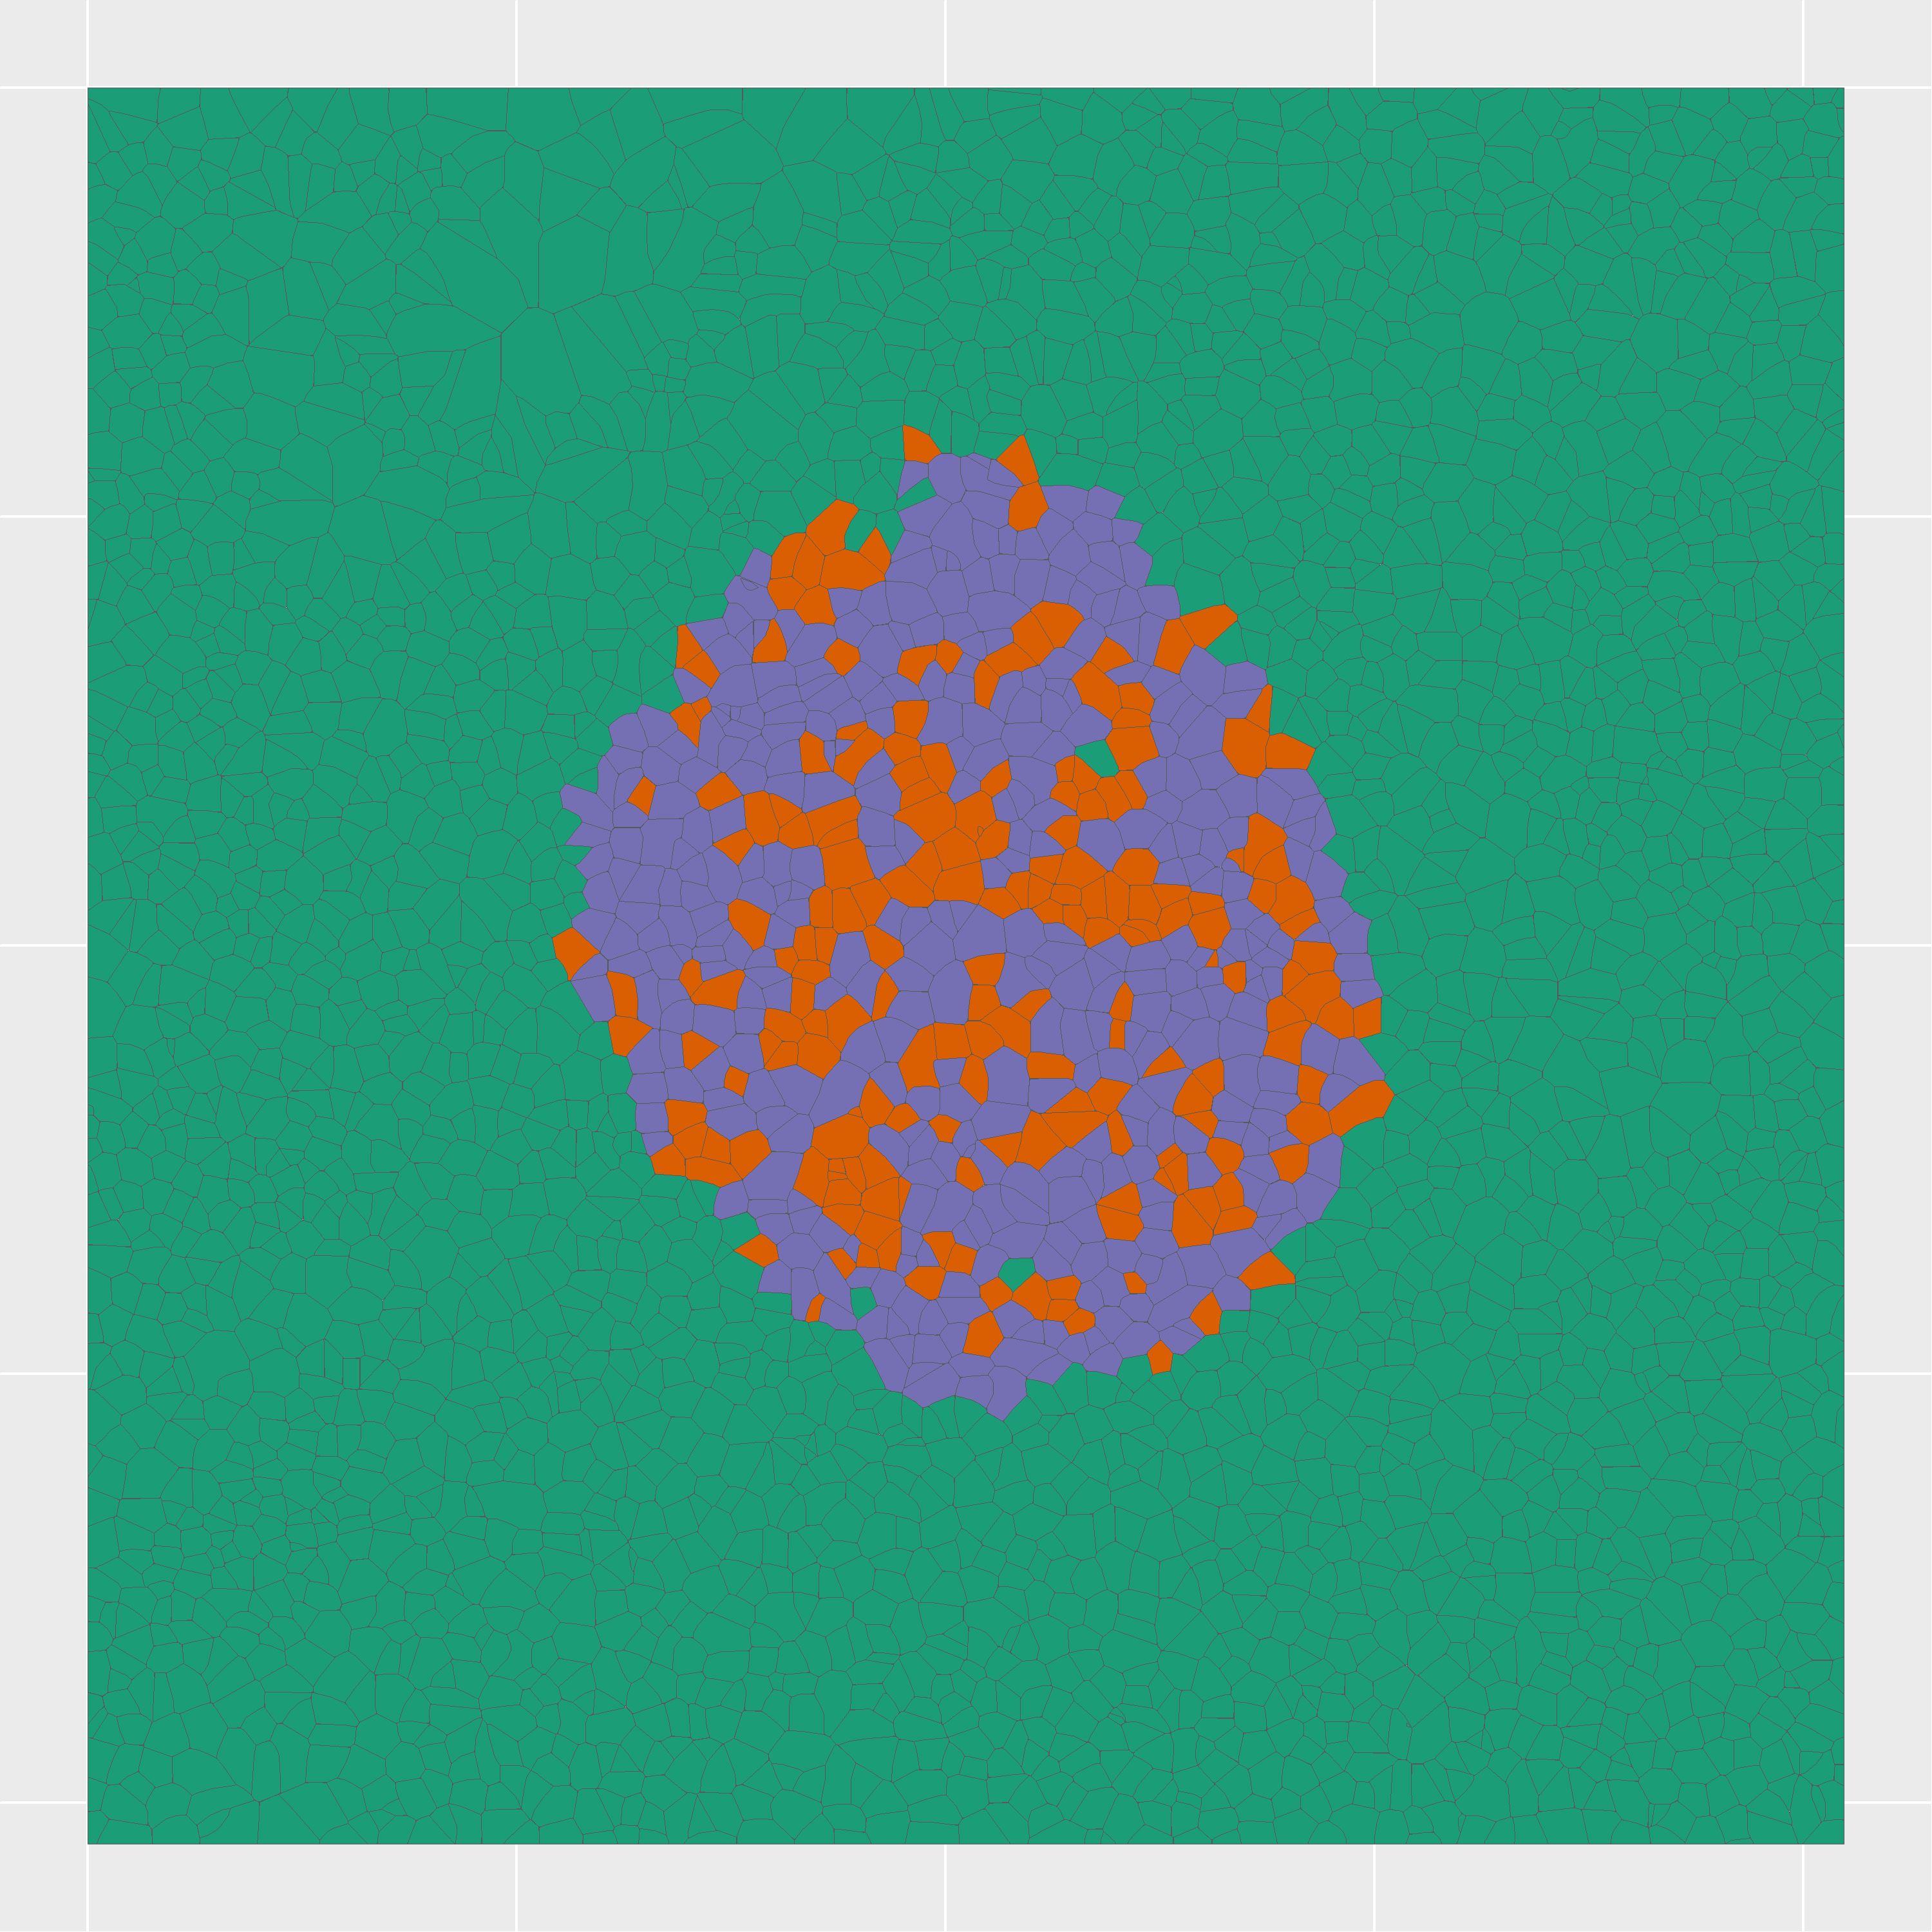

For each of 2,215 proteins passing quality filters, cell-type-adjusted relative abundance was calculated and visualized as spatial maps using ggplot2 with sf polygon geometries.